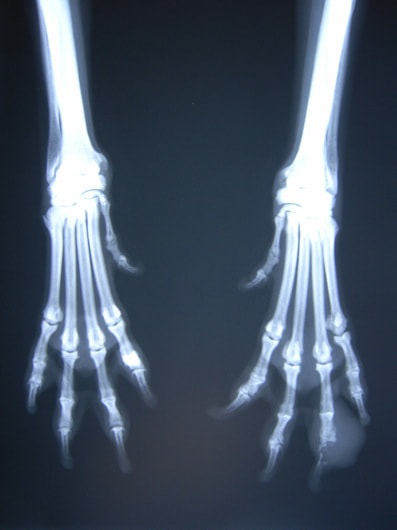

症例:右大腿骨遠位部の肉腫 クランバー・スパニエル 9歳 雌(未避妊)

2か月前から右後肢の完全挙上が認められ、消炎剤による内科治療で改善しないとのことで、他院から紹介来院した。

レントゲン検査

骨生検および病理組織検査

レントゲン検査所見から、骨もしくはその周囲組織に発生した腫瘍の可能性が考えられたため、病変部の細胞診検査およびジャムシディ生検針を用いた病変の骨生検を実施した。病理組織検査の結果、非上皮性の悪性腫瘍である“肉腫”と診断された。

内科治療に反応が乏しい四肢の跛行や疼痛は、本症例のように腫瘍が原因となっていることがあるため、レントゲン検査、骨生検等積極的に原因追及のための検査を実施することが必要である。骨の破壊を起こす悪性腫瘍は、非常に強い痛みを伴い、消炎鎮痛剤を用いても痛みを抑えることが困難となる。痛みの除去および腫瘍の治療のために断脚手術や抗がん剤等が必要となる場合があり、似た症状を示す整形外科疾患等とは治療法・予後が異なるため、その鑑別は重要である。